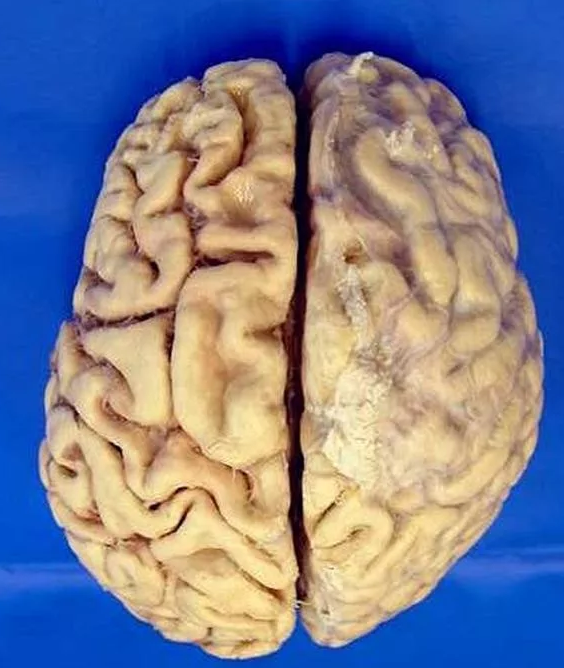

Болезнь Крейтцфельдта-Якоба, или "коровье бешенство"

Поражает кору головного или спинного мозга, нервные окончания. Эта болезнь считается проявлением губчатой энцефалопатии: мозг превращается в буквальном смысле в губку, что ведёт к потере зрения, слуха, речи, психическим заболеваниям, нарушению координации и т.д. Причиной её возникновения становятся так называемые прионы, или аномальные белки, которые безвредны, пока они в норме, но, преобразуясь в патогенные, запускают разрушительную болезнь мозга. А заболевание чаще всего спонтанное: возникает вроде как беспричинно.Второй вариант - генетическая мутация, это так называемая наследственная (или семейная) болезнь Крейтцфельдта-Якоба. И третий, но совершенно незначительный по числу заболевших вариант - заражение через кровь, от попадания в неё поврежденных частичек от больного человека, что может произойти при некоторых медицинских процедурах - вроде пересадки кожи или роговицы. И ведь современная медицина против этого заболевания бессильна: возможна только симптоматическая терапия, приносящая облегчение и продлевающая жизнь, но - ненадолго.Смерть наступает в 85 процентов случаев при лёгкой форме (то есть у пятнадцати из ста есть небольшой шанс выкарабкаться с помощью поддерживающих лекарств), а вот при тяжёлой форме излечиться нельзя.